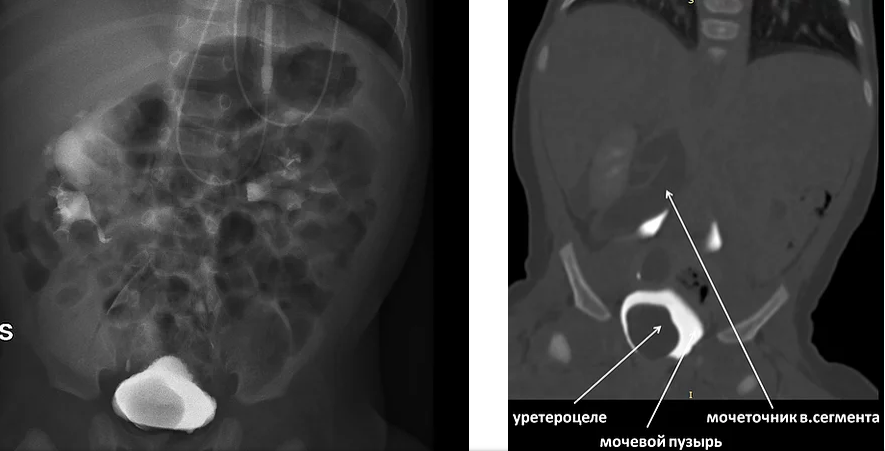

Операции уретероцеле

Операции уретероцеле 97 фото